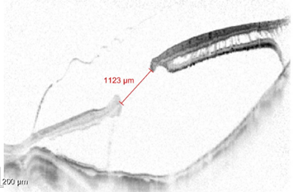

63 岁的林阿姨(化名)是一位高校退休教授,高度近视 30 多年,度数从 300 度发展到 2000 度。最近几年,更让她担忧的事情发生了——左眼黄斑区出现了一个 1123 微米的大裂孔。「眼前一片发黑,什么都看不见了。」林阿姨回忆。她的这种症状有个更专业的术语,叫眼前手动,这表示她连视力表最大的字母也看不到,也就是视力达不到 0.1。

「在以往的观念中,直径大于 400 微米的黄斑裂孔,闭合难度就增加,而高度近视黄斑裂孔,更是属于难治性黄斑裂孔,眼轴越长,黄斑裂孔往往越大,且闭合难度也增加。」 浙江省眼科医院(温州医科大学附属眼视光医院)杭州院区眼底病临床中心副主任张赟在看到林阿姨眼底情况的第一眼时,就感受到手术的难度。

不过,张赟根据阿姨的情况选择了黄斑区内界膜翻转技术。在 OCT 检查中,黄斑裂孔犹如一条鸿沟,将内界膜翻转连接,让裂孔两端「不远千里来相会」。林阿姨的手术持续了半个多小时,最终成功完成。